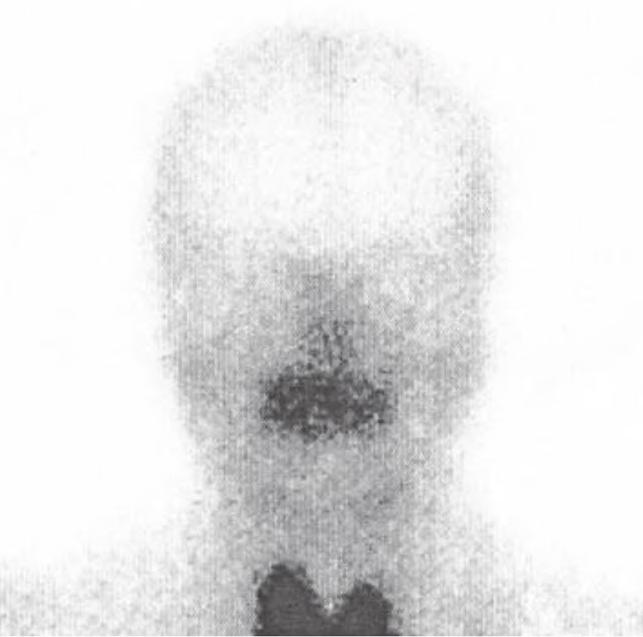

Scyntygrafia ślinianek wykonywana jest z użyciem 99mTc, a wskazaniami do jej wykonania są guzy ślinianek, zaburzenia wydzielania śliny (zwłaszcza jednostronne) oraz monitorowanie funkcji ślinianek po uprzedniej radioterapii (ryc. 2.43).

Czynnościowa scyntygrafia prawidłowych ślinianek: A – w spoczynku (widoczny wychwyt w śliniankach); B – po podaniu soku z cytryny (brak wychwytu w śliniankach).